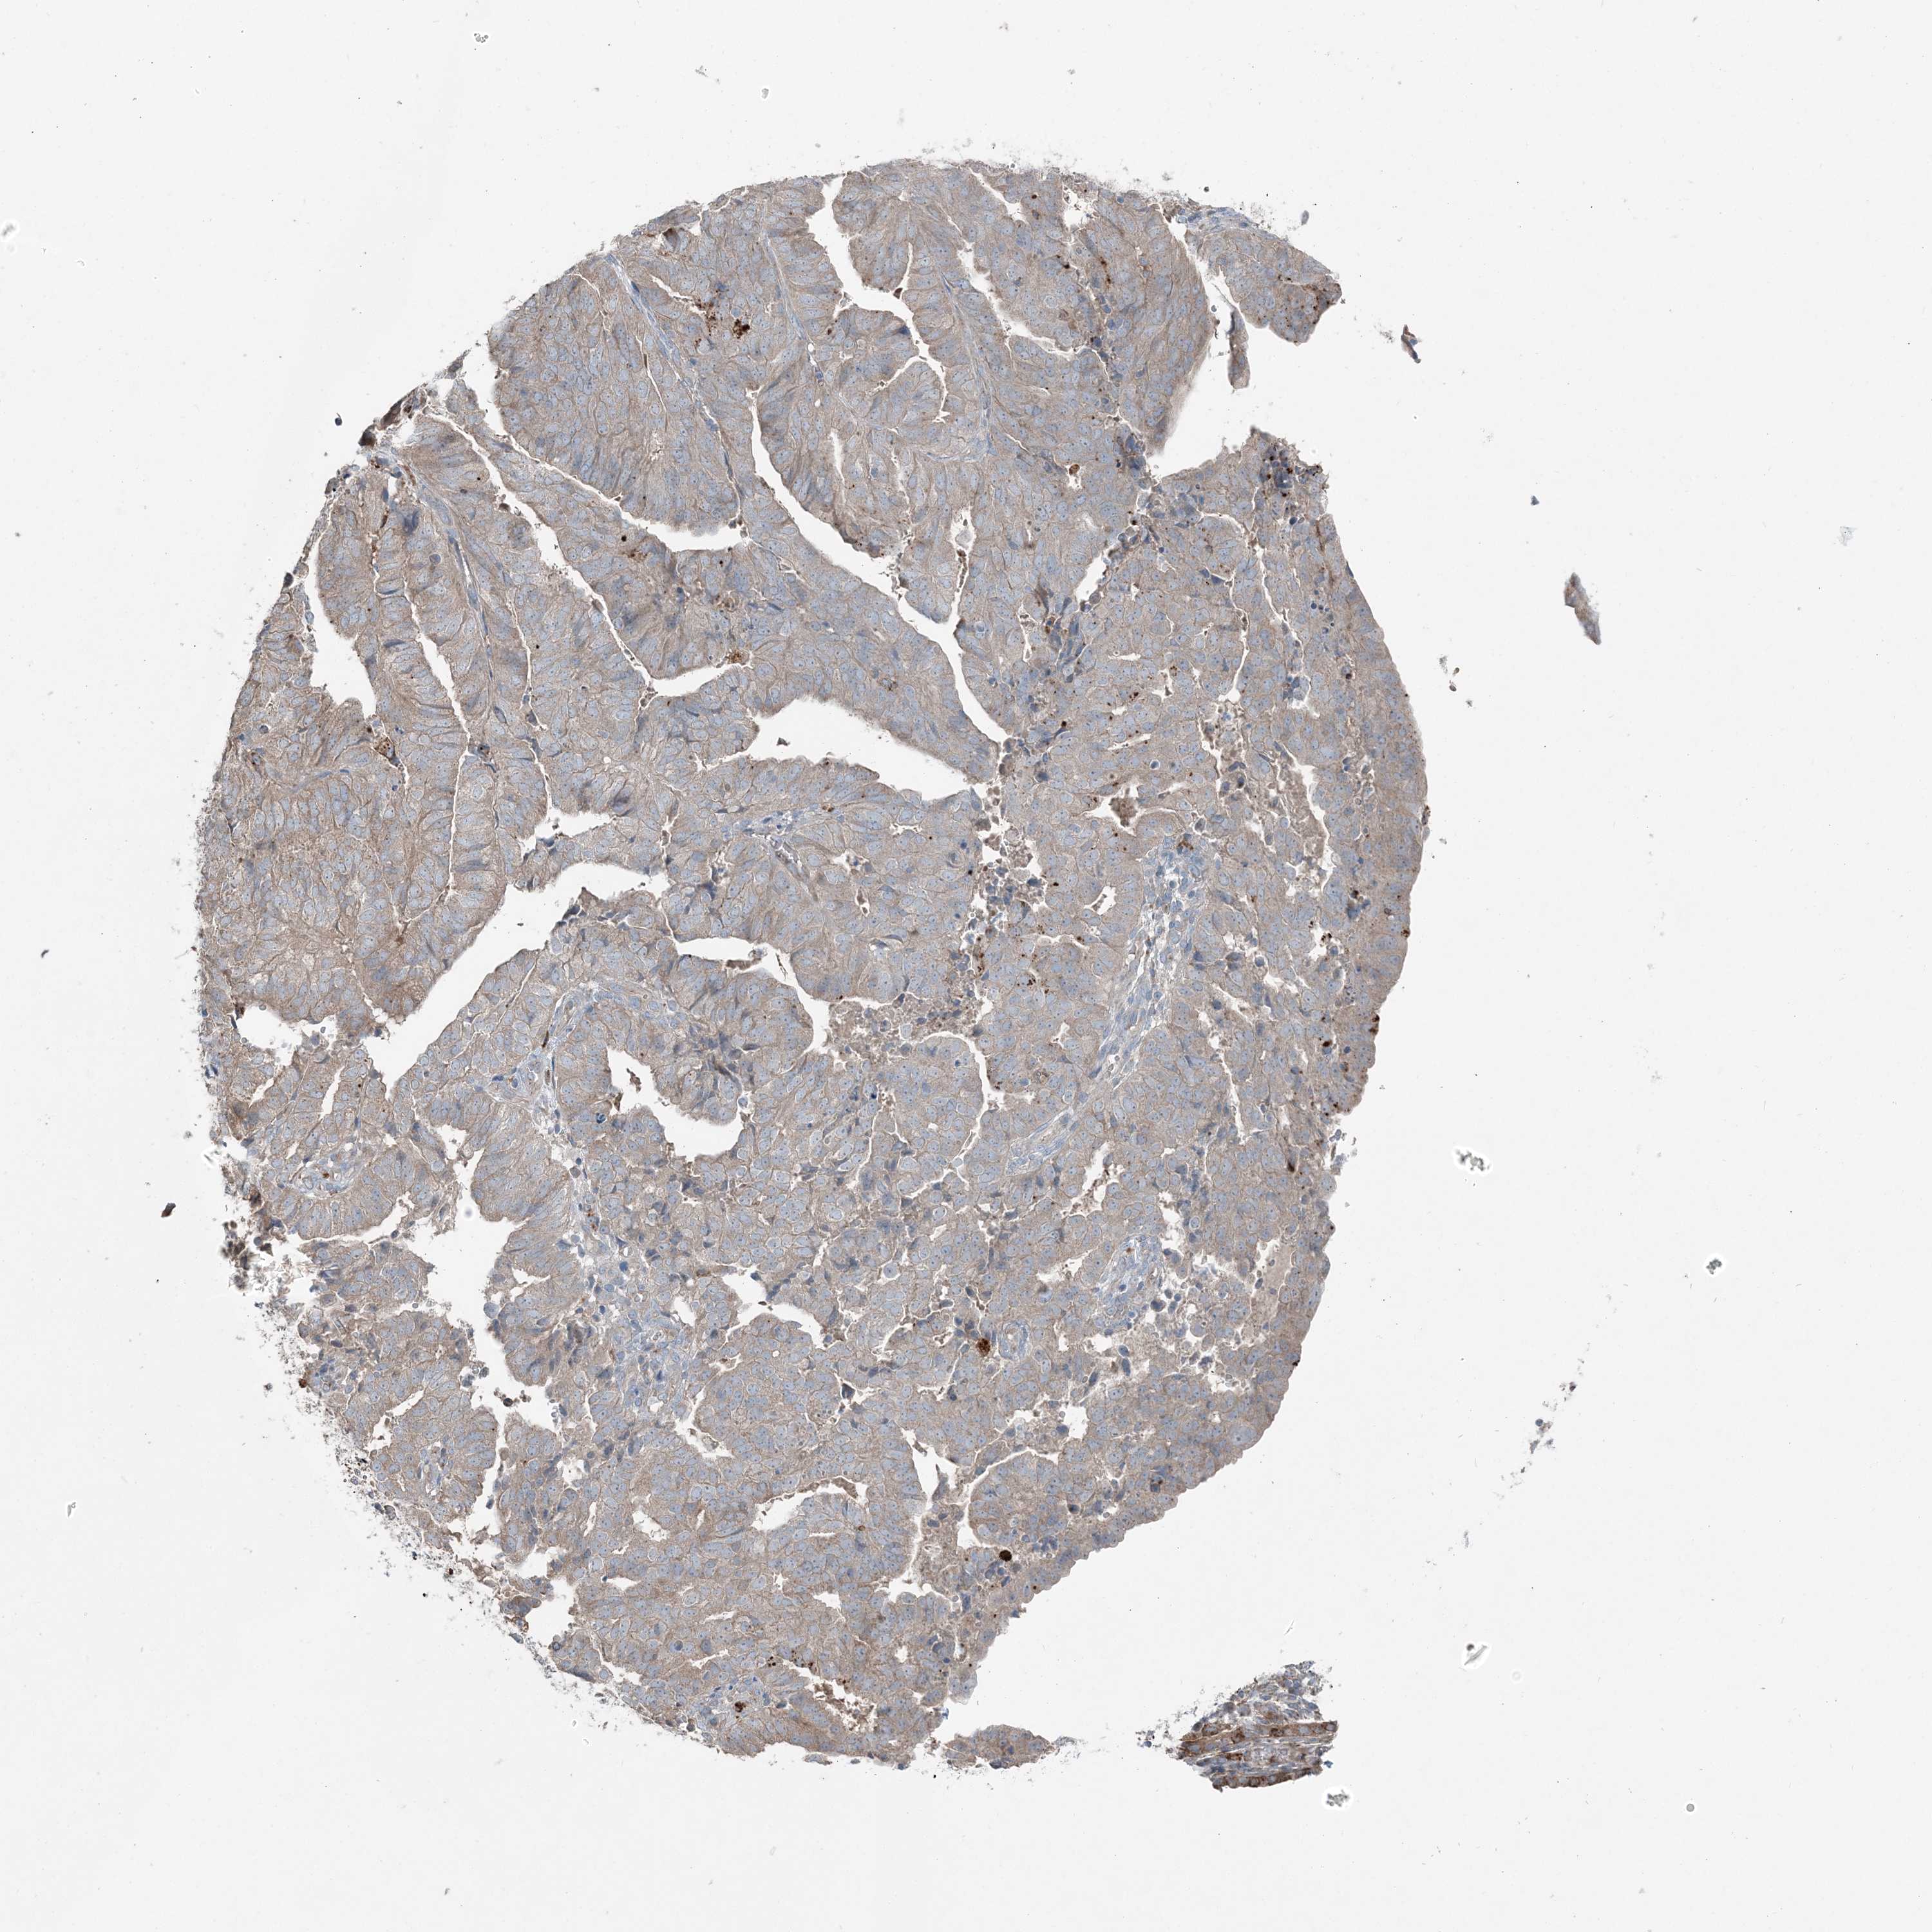

ENDOMETRIAL CANCER - Protein expressioni

A mouse-over function shows sample information and annotation data. Click on an image to view it in a full screen mode. Samples can be filtered based on level of antibody staining by selecting one or several of the following categories: high, medium, low and not detected. The assay and annotation is described here.

Note that samples used for immunohistochemistry by the Human Protein Atlas do not correspond to samples in the TCGA dataset.

Antibody stainingi

Antibody staining in the annotated cell types in the current human tissue is reported as not detected, low, medium, or high, based on conventional immunohistochemistry profiling in selected tissues. This score is based on the combination of the staining intensity and fraction of stained cells.

Each image is clickable and will lead to virtual microscopy that enables deeper exploration of all samples and also displays staining intensity scores, fraction scores and subcellular localization as well as patient and tissue information for each sample.

Antibody HPA036492

Antibody HPA036668

Staining

High

Medium

Low

Not detected

Intensity

Strong

Moderate

Weak

Negative

Quantity

>75%

75%-25%

<25%

None

Location

Nuclear

Cytoplasmic/membranous

Cytoplasmic/membranous,nuclear

Adenocarcinoma, NOS